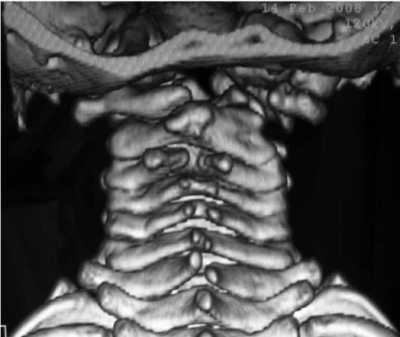

Рис. 5.2 Ребенок 7 лет с костной формой кривошеи на фоне порока развития.

А, Б – 3D КТ реконструкция передняя и задняя проекция. Гипоплазия суставной поверхности и аплазия задней полудуги атланта. CI смещен вправо и вниз. Деформация частично компенсируется полупозвонком CIII справа, который вызывает наклон CII влево и блокирование латеральной нестабильности CI.